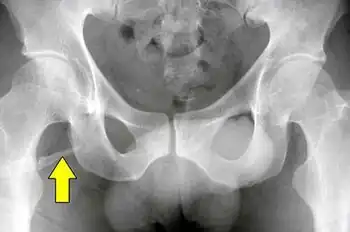

Radiograph showing a pelvic digit

A pelvic digit, pelvic finger, or pelvic rib is a rare congenital abnormality in humans, in which bone tissue develops in the soft tissue near the pelvis, resembling a rib or finger and often divided into one or more segments with pseudo-articulations. Pelvic digits are typically benign and asymptomatic, and are usually discovered accidentally. Approximately 41 cases have been reported.[1]